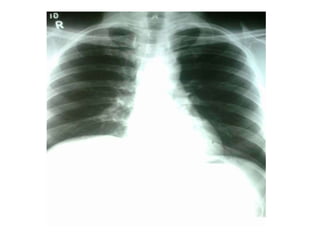

• A unilateral diaphragmatic paralysis is usually

asymptomatic and is most often an incidental

finding on x-ray. If both sides are paralysed, the

patient may experience poor exercise tolerance,

orthopnoea and fatigue.

• Lung function tests will show a restrictive deficit.